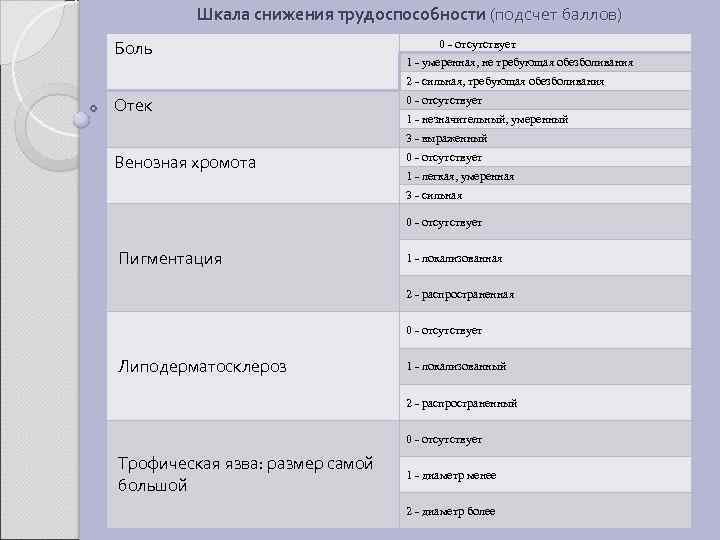

Шкала снижения трудоспособности (подсчет баллов) Боль 0 - отсутствует 1 - умеренная, не требующая обезболивания 2 - сильная, требующая обезболивания Отек 0 - отсутствует 1 - незначительный, умеренный 3 - выраженный Венозная хромота 0 - отсутствует 1 - легкая, умеренная 3 - сильная 0 - отсутствует Пигментация 1 - локализованная 2 - распространенная 0 - отсутствует Липодерматосклероз 1 - локализованный 2 - распространенный 0 - отсутствует Трофическая язва: размер самой большой 1 - диаметр менее 2 - диаметр более